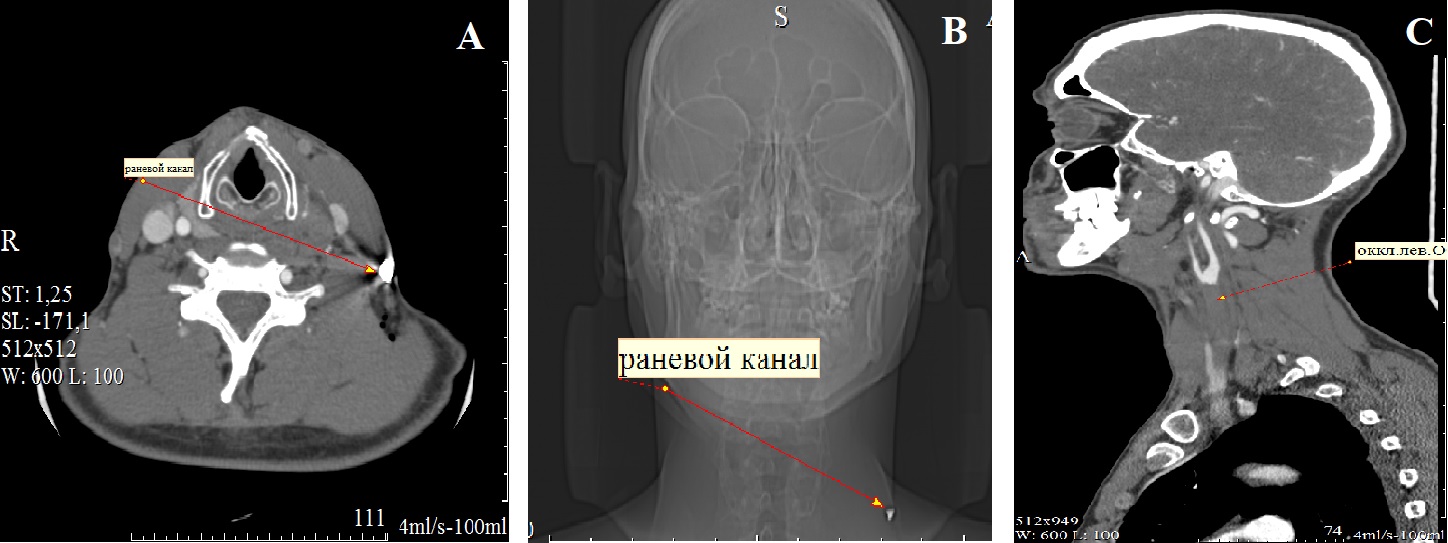

Рисунок 1 - Компьютерная томография шеи: ход раневого канала во второй зоне справа налево латеральнее ствола левой общей сонной артерии с фрагментом ранящего снаряда в конце раневого канала (А, В); в ангиографическом режиме видны тромботические массы в стволе левой общей сонной артерии до бифуркации (С)